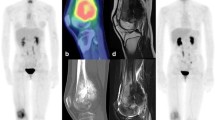

The posterior distributions of AUC, sensitivity, specificity, accuracy, positive predictive value, and negative predictive value for 18F-FDG PET and 18F-FDG PET/CT are summarized (combined and separately) in Table 4. For the combined modalities, the posterior mean (95 % HPD interval) for AUC was 0.92 (0.88, 0.96) and for sensitivity, specificity, accuracy, positive predictive value, and negative predictive value were 0.96 (0.90, 1.00), 0.77 (0.68, 0.86), 0.88 (0.85, 0.91), 0.86 (0.77, 0.94), and 0.91 (0.83, 0.99), respectively. A trend toward enhanced performance for PET/CT when compared to a dedicated PET was present, but failed to attain statistical significance. When assessing the two modalities separately, AUC, specificity, accuracy, and positive predictive values were higher for 18F-FDG PET/CT compared with 18F-FDG PET (Table 4 and Fig. 4). In addition, the partial AUC, which is restricted to the domain of the ROC curve yielding at least 80 % specificity, was also higher for 18F-FDG PET/CT [0.17 (0.15, 0.19)] compared with 18F-FDG PET [0.10 (0.04, 0.16)].

Forest plots for a sensitivity, b specificity, c accuracy, d positive predictive value, and e negative predictive value depicting the posterior means and 95 % HPD intervals obtained from meta-analysis of diagnostic performance for differentiating between malignant and benign soft tissue musculoskeletal lesions. Results for malignant lesions were not reported for the Ahmed et al. [12] study